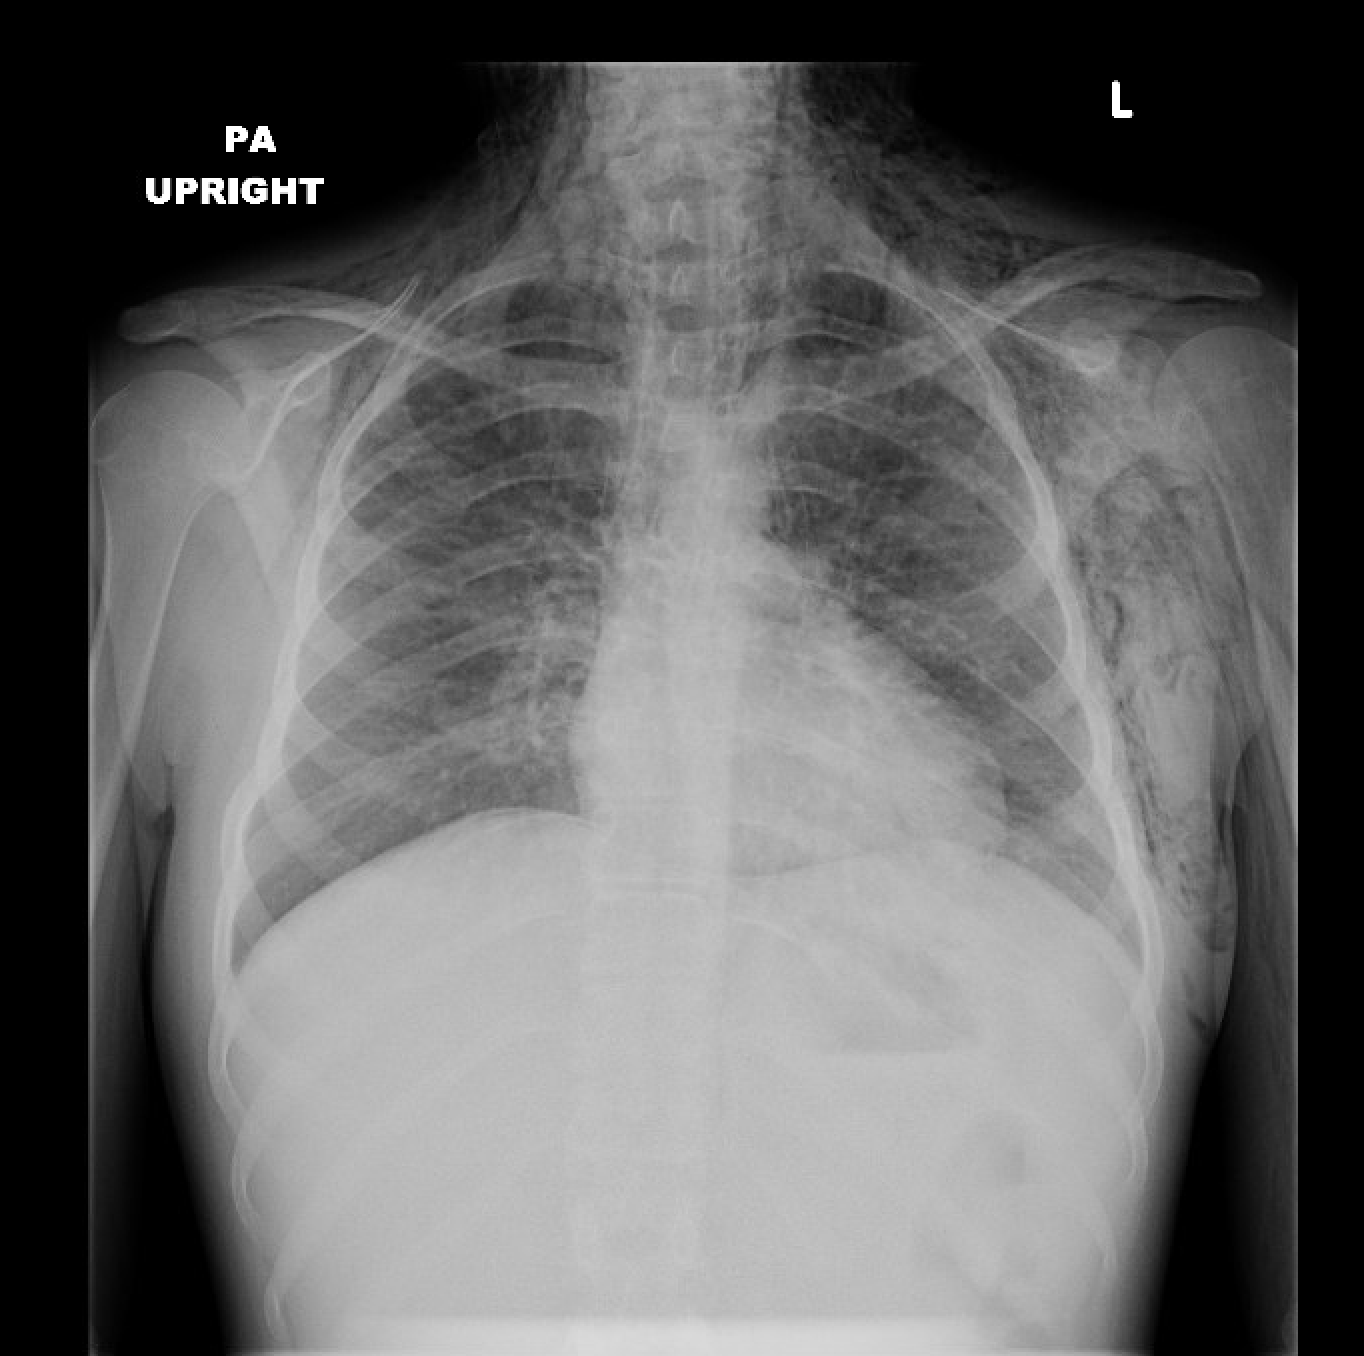

Case 9: Find the abnormality:

Case 9 Answer: This x-ray is NORMAL. It looks like this patient has a left pneumothorax on first glance, but the pleural line you think you see is actually a skin fold. (7) Notice that the pulmonary vessels extend to the outer edge of the lung fields.